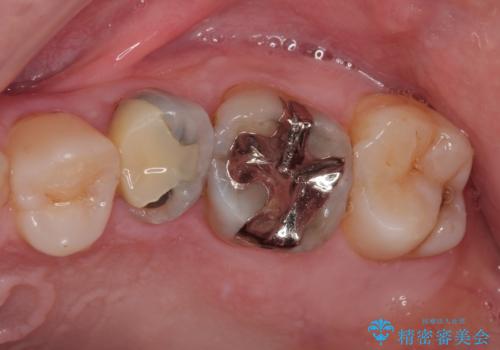

- 左上の小臼歯の詰め物が欠けたことを主訴に、50代男性の患者様が来院されました。

「最近、食事の際に違和感がある」「詰め物が欠けている気がする」とのことでした。

精密検査を行ったところ、上顎左側第二小臼歯のインレー(詰め物)が欠け、その内部に虫歯が進行している状態でした。幸いにも虫歯は神経まで達しておらず、神経を残した治療が可能と判断しました。